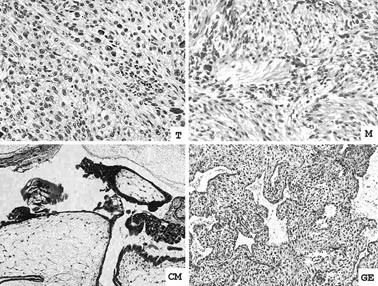

Figure 1

Representative histology of case #5. T: placental site trophoblastic tumor (PSTT) (H&E × 40), M: normal myometrium adjacent to the PSTT (H&E, × 40), CM: complete mole (H&E, × 20), GE: gestational endometrium associated with complete mole (H&E, × 20).